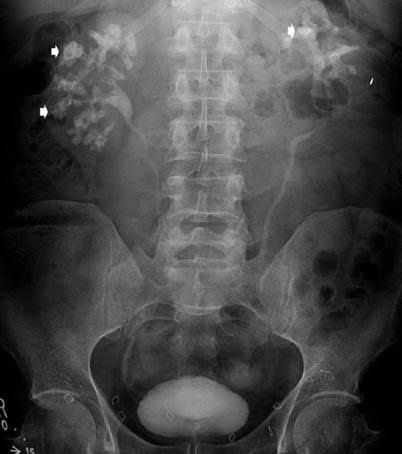

Kidney stones (also called renal calculi, nephrolithiasis or urolithiasis) are hard deposits made of minerals and salts that form inside your kidneys. Diet, excess body weight, some medical conditions, and certain supplements and medications are among the many causes of kidney stones.